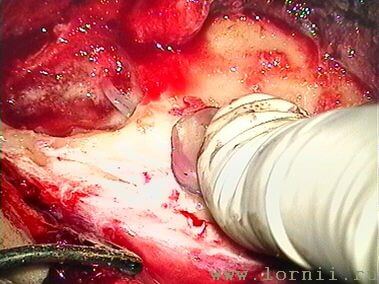

У пациентов с аномалией развития уха и после радикальной операции катушка импланта была установлена в круглое окно (рис. 13, 15, 16). Для этого крепление катушки подворачивали (рис. 14). Далее укладывали фасцию височной мышцы в нишу окна улитки (рис. 15), затем на фасцию устанавливали катушку импланта и подворачивали края фасции. Фиксация конструкции обеспечивалась полоской аутохряща из ушной раковины пациентки (рис. 16).